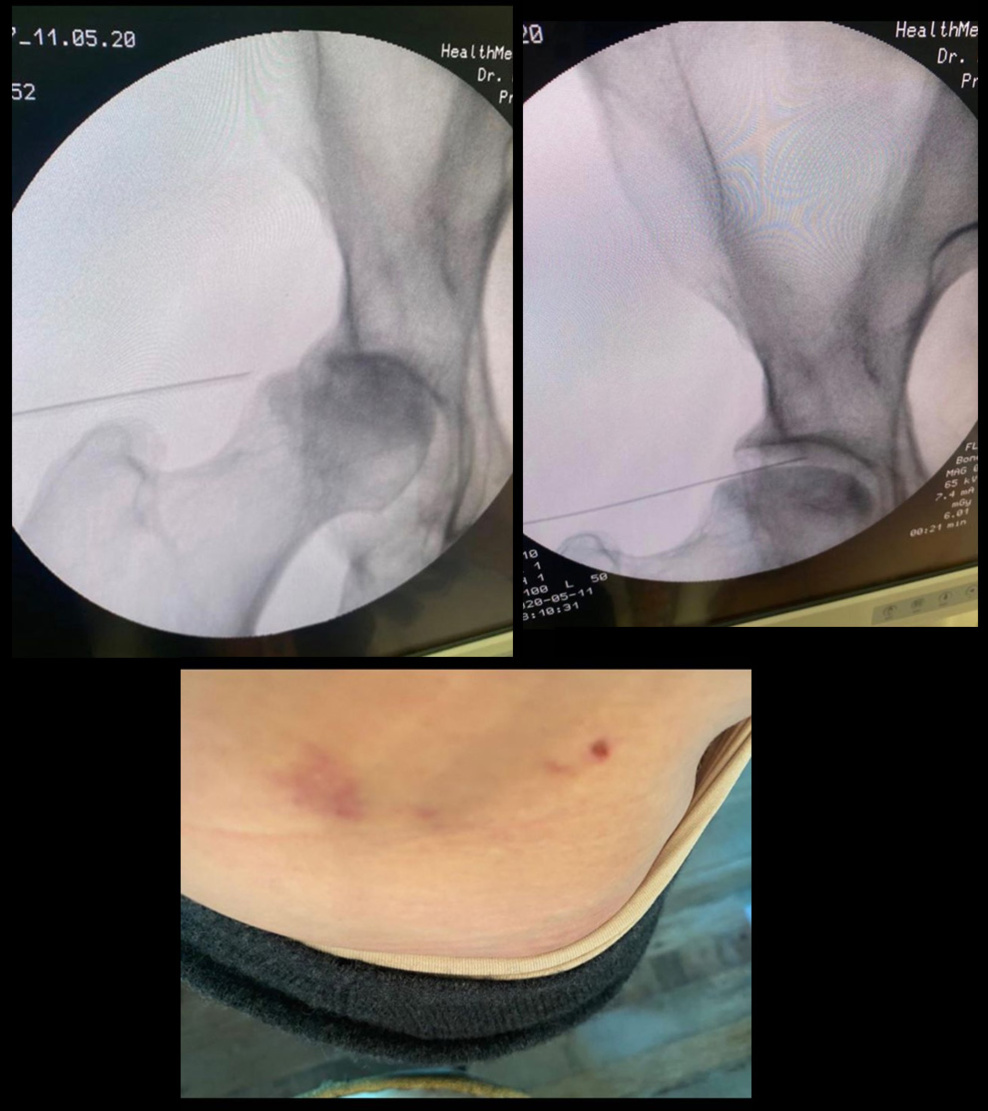

On y apprend également qu'à cette époque, une équipe française a mis au point un implant 3D composés de facteurs de croissance qui vont permettre la régénération de l’os et un hydrogel avec des cellules souches dérivées de la moelle osseuse du patient et qui va régénérer le cartilage. Cette intervention n'a donc rien d'anodin puisqu'elle nécessite un prélèvement de moelle osseuse. Les clichés du dos de Madonna et ses ecchymoses semblent confirmer qu'elle a bien subie cette intervention.

Selon un de nos fidèle lecteur qui est du métier, les clichés que l'on voit avec l'aiguille sont des images de sa hanche. Hanche qui d'après lui est en très mauvais état et qui nécessitera certainement une prothèse :-( Il ajoute qu'elle a du beaucoup en souffrir...